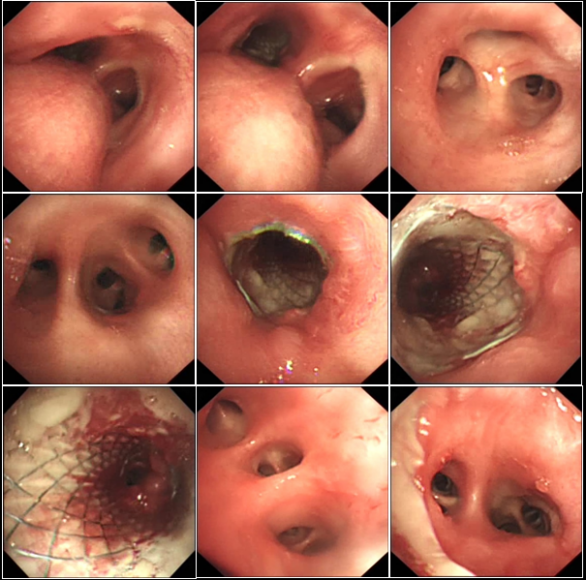

病例7:49岁女性患者,因反复咳嗽咳痰1年、咳血丝痰伴气促20余天入院,入院后需端坐呼吸,气促明显,高流量氧疗情况下SpO2仍低于80%。胸部CT提示右肺上叶尖段周围型肺癌伴全身多发转移;支气管镜检查示气管下段肿瘤外压性狭窄并侵犯黏膜,双侧支气管开口狭窄,进镜后患者呼吸困难加重,紧急气管插管机械通气,随后在左主支气管入金属支架(图11),快速解除气道阻塞。左主支气管支架入术后反复大量脓血痰病理诊断为低分化腺癌,ALK基因变异。患者反复发热、低氧发作,需反复纤支镜吸痰;双上肢、颜面部浮肿明显,需反复心包、双侧胸腔抽液;白细胞明显升高、贫血,间断需升压药维持血压;停机不耐受(3~5 min)。患者经过积极的抗感染及基因靶向治疗后,病情逐渐好转,成功拔管并脱离呼吸机支持,顺利转出RICU。复查纤支镜提示气道通畅、炎症明显改善(图12),影像学改善(图13)体力状况PS评分显著下降,达到临床稳定水平,随后接受后续抗肿瘤综合治疗

图片

11  患者胸部CT及纤支镜下置入支架

12  出院前复查纤支镜

13  治疗前后胸部CT对比

病例8:53岁女性患者,因反复活动后气促12年、再发5月余入院,胸部CT(图14)+气道重构示气管隆突部结节样软组织密影(27 mm×20 mm×21 mm),食管可疑受累。RICU监护下支气管镜检查见气管下段、隆突前巨大新生物,管腔堵塞,遮挡双主支气管(图15)。在气管插管呼吸机支持下行电圈套套扎术+射频消融术+钳取等介入处理(图16),成功解除气道阻塞。病理诊断为肺上皮-肌上皮癌,免疫组化提示CK7及CD117(腺上皮成分+),SMA、p63及Calponin(肌上皮成分+)等,为后续治疗提供了依据。

14  患者胸部CT

15  RICU监护下纤支镜检查

16  呼吸机支持下介入治疗